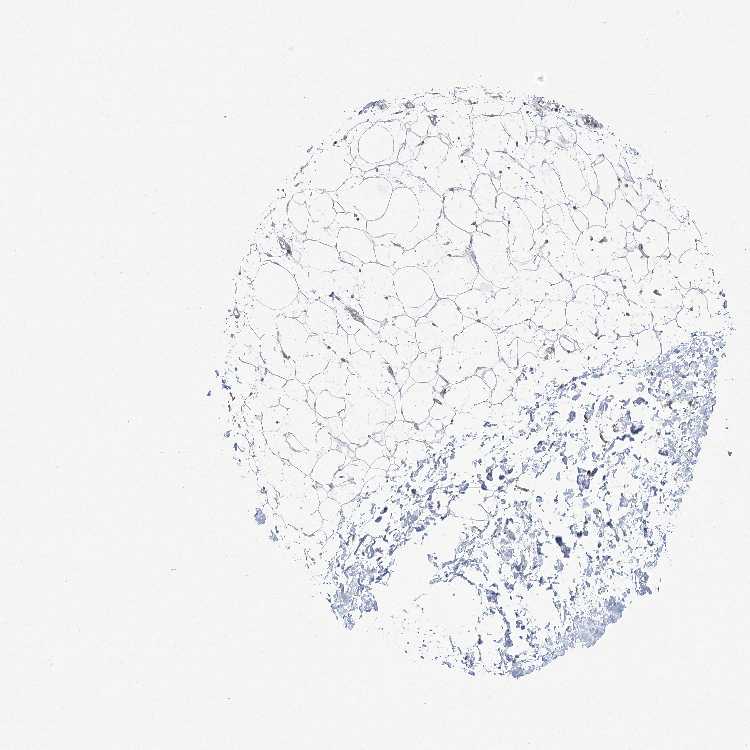

SOFT TISSUE 1 - Antibody stainingi

Antibody staining in the annotated cell types in the current human tissue is reported as not detected, low, medium, or high, based on conventional immunohistochemistry profiling in selected tissues. This score is based on the combination of the staining intensity and fraction of stained cells.

Each image is clickable and will lead to virtual microscopy that enables deeper exploration of all samples and also displays staining intensity scores, fraction scores and subcellular localization as well as patient and tissue information for each sample.

Antibody HPA036342Antibody HPA036343

Chondrocytes Not detected-

Fibroblasts LowNot detected

Peripheral nerve Not detected-

SOFT TISSUE 2 - Antibody stainingi

Antibody HPA036342

Chondrocytes Low

Fibroblasts Low

Peripheral nerve Not detected